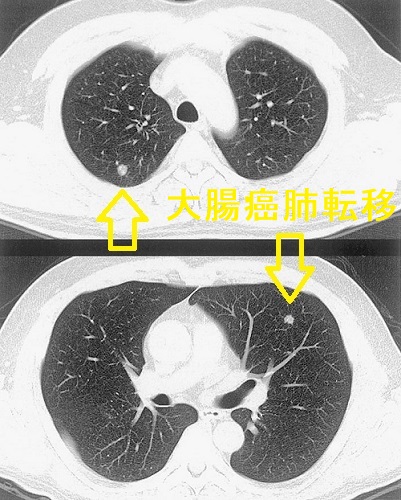

甲状腺癌以外の癌からの肺転移の可能性もあります。甲状腺癌と同時に他臓器の癌(重複癌)を持っていれば可能性は高くなります。特に、多発性肺転移の形態をとる大腸がんの肺転移は紛らわしいです。

もちろんサイログロブリンなどの腫瘍マーカーも鑑別診断の参考になりますが、元々、橋本病の自己抗体の一つ抗サイログロブリン抗体(Tg-Ab)]を持っている方では、サイログロブリンが実際の値よりも低くなるため、あてになりません(抗サイログロブリン抗体(Tg-Ab) )。

大腸癌の肺転移は、肺以外に転移が無く、肺切除可能な場合は予後が良いので肺切除になります。甲状腺癌の肺転移と根本的に治療法が異なるため見逃してはいけません。

大腸癌肺転移